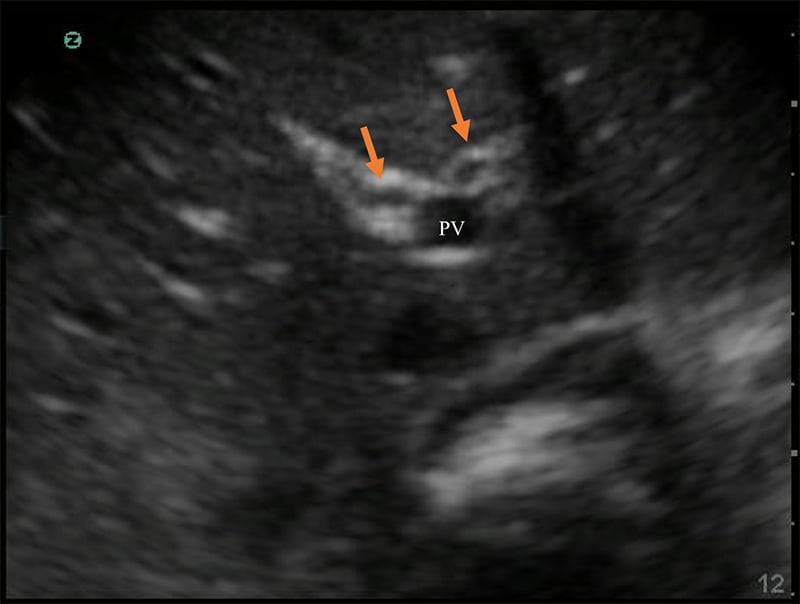

Figure 9. “Exclamation point” revealing the gallbladder (GB) in long axis with the bright-walled portal vein (PV) in short axis.

- The larger, bright-walled portal vein will often be seen with the two smaller structures of the portal triad in the same cross section, a hepatic arterial branch and common bile duct.

Figure 10. The portal triad seen in short axis. The portal vein (PV) is the largest, while the hepatic artery and bile duct (arrows) are much smaller and often indistinguishable without color Doppler.